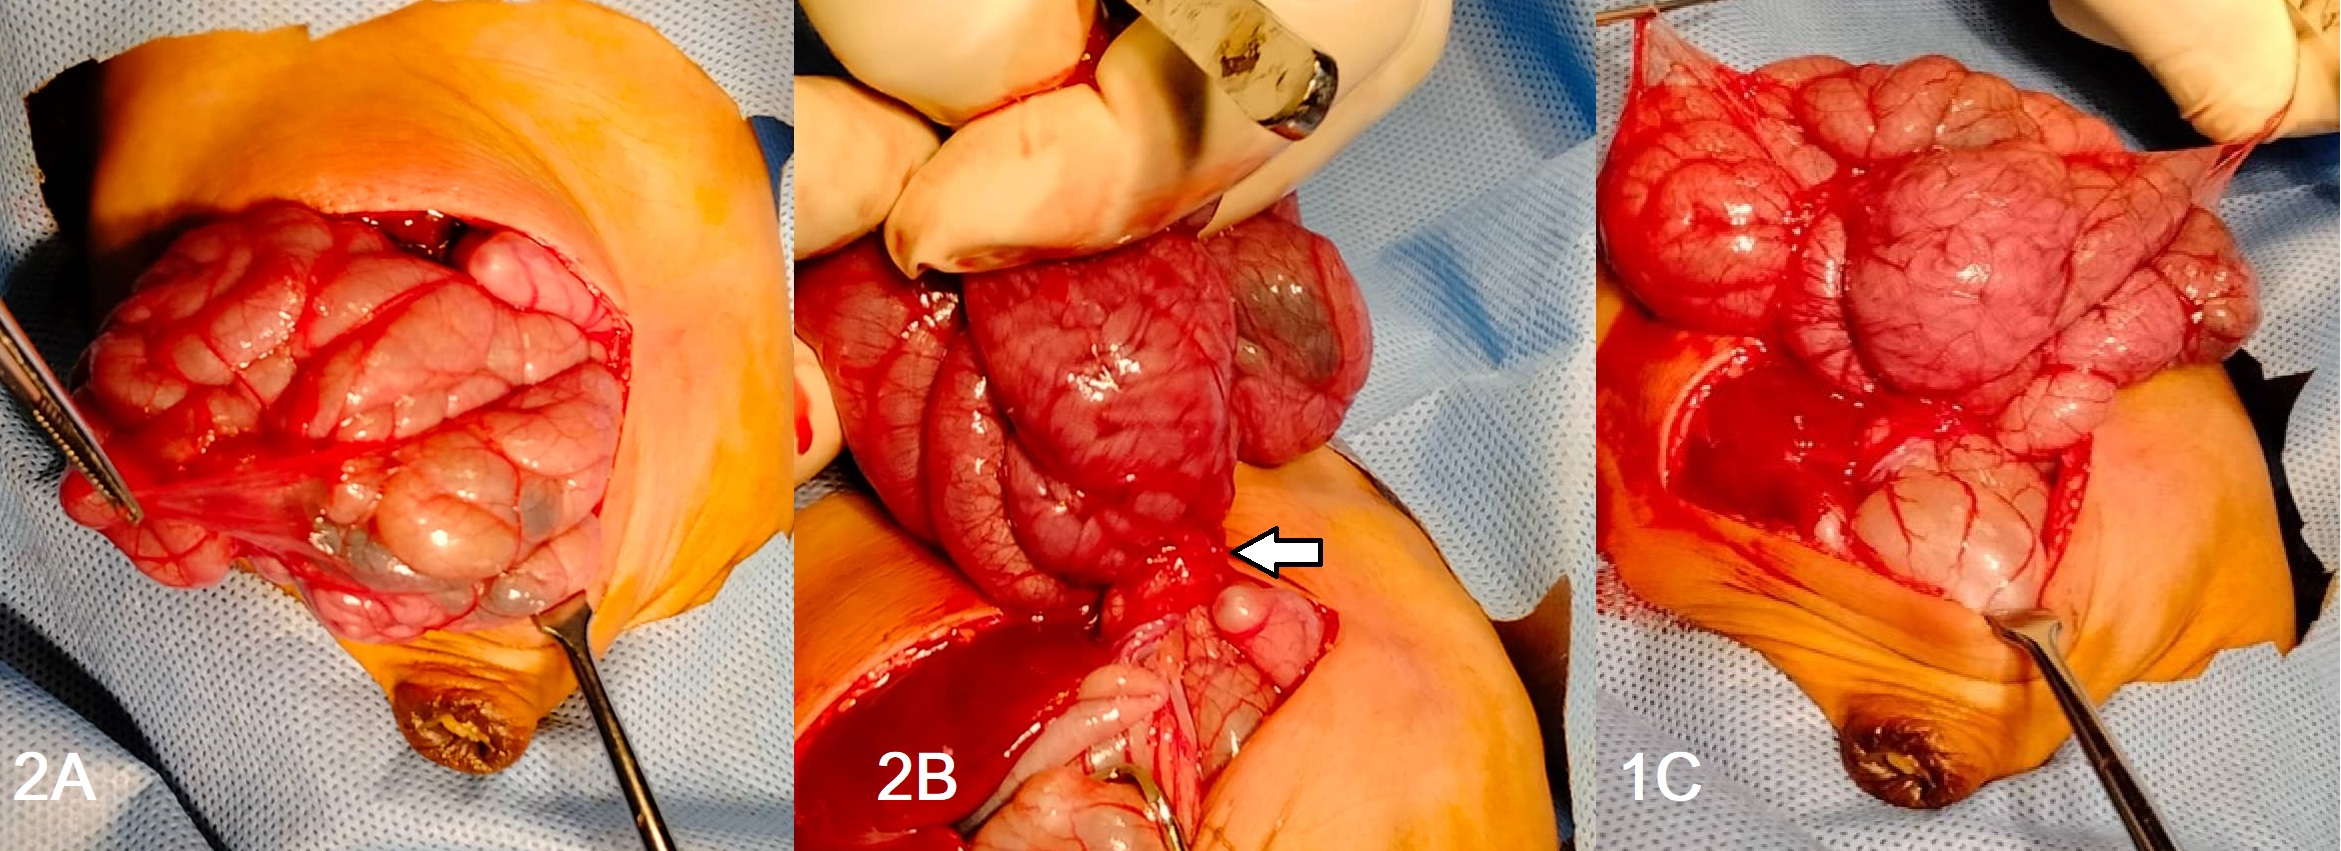

Plain abdominal x-rays showed a grossly dilated stomach and paucity of gas in the distal bowel (Fig. 1A). Abdominal distension resolved after 2 days while NGT drainage became clear and the baby started passing stools. He was allowed dextrose water via NGT which was tolerated for 5 days before the residual became bilious again.

The upper GI series suggested dilated stomach and proximal duodenum up to the third part; there was delayed passage of minimal contrast distally (Fig. 1B, 1C). The abdominal ultrasound was unremarkable due to the gaseous distension.

Imaging studies are mostly inconclusive. [9] Plain abdominal x-rays may be unremarkable, or it may also show dilated stomach and proximal bowel, there may be a paucity of gas in the distal bowel, or crowding of small bowel gas shadows. [5], [7] If there are no signs of complete obstruction, contrast gastrointestinal x-ray series may show delayed intestinal transit time. However, no definite transition point is usually seen. Abdominal ultrasound has been reported to show a cauliflower sign depicting the encased bowel on a stalk of its narrow mesentery base. This is usually obscured if there is proximal dilatation and excess intraluminal gas but may be more prominent in the presence of ascites.[7], [11] In adults, a contrast-enhanced CT scan may be the best option for investigating suspicion of an abdominal cocoon but the risk of exposure to such high doses of radiation, makes it unattractive in neonates.

Figure 1

A) Plain abdominal radiograph showing grossly dilated stomach and paucity of gas in the distal bowel, B and C) Barium meal and follow-through showing dilated stomach and duodenum and jejunum